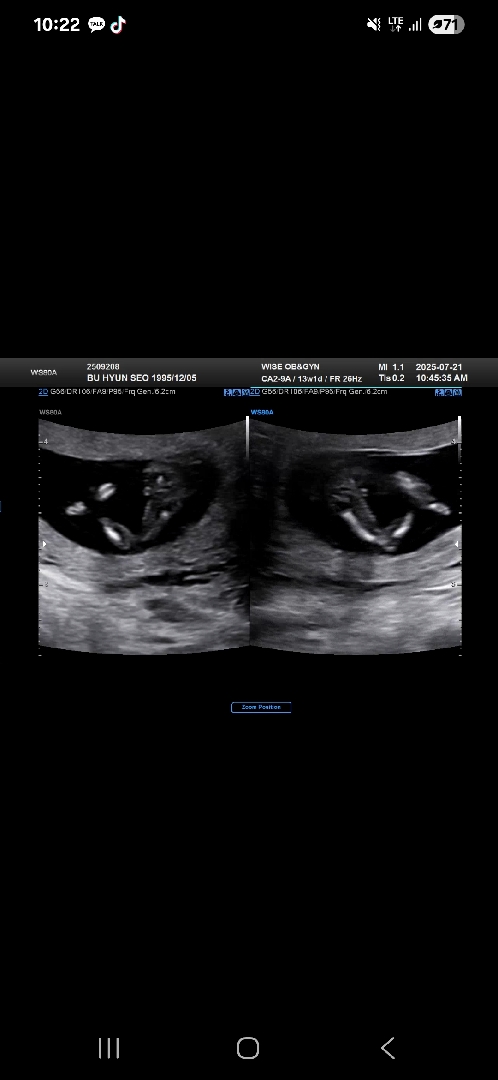

13주 성별이 궁금해요 다리 사이에 저것이...

아들 둘인 엄마는 딸을 기도하고 또 기도하는 중인데 혹시 저 다리 사이에 보이는 것이 ㄱ..ㅗ...환...인가요...?😭😭😭 첫째둘째때는 선생님께서 말씀하시기 전에 앗...🌶가 보인다 생각했는데 아들 맞았거든요...ㅎㅎ 제가 생각하는 고환이....맞나요.....?ㅠㅠ